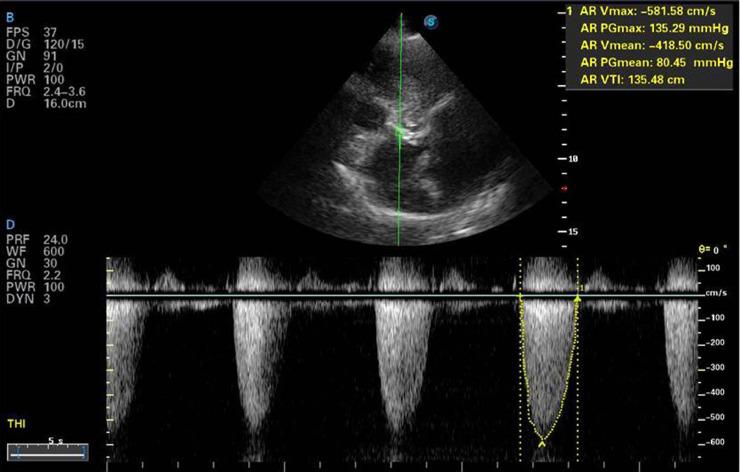

Coronary artery fistulas are anomalous connections between one or two coronary arteries with either a cardiac chamber or any major blood vessels (coronary sinus, superior vena cava, pulmonary veins and pulmonary artery). It is rarely reported, occurring only in 0.1%-0.2% of patients who undergo coronary angiography. We report a very rare case where myocardial ischaemia may have resulted from the presence of coronary artery fistula, significant coronary artery stenosis and severe aortic valve stenosis. Transthoracic echocardiography showed severe aortic stenosis, while coronary angiography showed a tortuous coronary artery fistula originating from the proximal left anterior descending artery, with a single opening in the main pulmonary artery. Angiography also showed significant stenosis in the middle of the left anterior descending artery. Coronary artery fistula with concomitant significant coronary atherosclerosis and severe aortic stenosis requires optimal therapeutic planning.

冠状动脉瘘是一条或两条冠状动脉与心腔或任何大血管(冠状窦、上腔静脉、肺静脉和肺动脉)之间的异常连接。其报道很少,仅在接受冠状动脉造影的患者中0.1%-0.2%出现。我们报告了一例非常罕见的病例,其中心肌缺血可能是由冠状动脉瘘、显著的冠状动脉狭窄和严重的主动脉瓣狭窄共同导致的。经胸超声心动图显示严重的主动脉狭窄,而冠状动脉造影显示一条迂曲的冠状动脉瘘起源于左前降支近端,在主肺动脉有单一开口。血管造影还显示左前降支中段有显著狭窄。伴有显著冠状动脉粥样硬化和严重主动脉狭窄的冠状动脉瘘需要优化治疗方案。